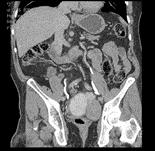

男,68岁,请根据所示图像,选择最可能诊断 ( )A、膀胱癌B、膀胱憩室C、先天性巨输尿管D、膀胱假性憩室E、输尿管囊肿

问题 男,68岁,请根据所示图像,选择最可能诊断 ( )

选项 A、膀胱癌 B、膀胱憩室 C、先天性巨输尿管 D、膀胱假性憩室 E、输尿管囊肿

答案 B